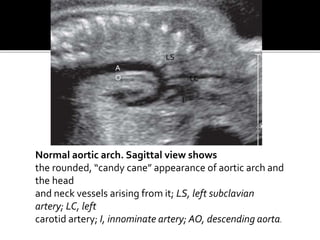

Normal aortic arch. Sagittal view shows

the rounded, “candy cane” appearance of aortic arch and

the head

and neck vessels arising from it; LS, left subclavian

artery; LC, left

carotid artery; I, innominate artery; AO, descending aorta.